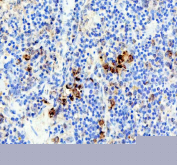

IHC staining of FFPE mouse spleen tissue with Neutrophil Elastase antibody, HRP-labeled secondary and DAB substrate. HIER: boil tissue sections in pH6 citrate buffer for 20 min and allow to cool before testing.